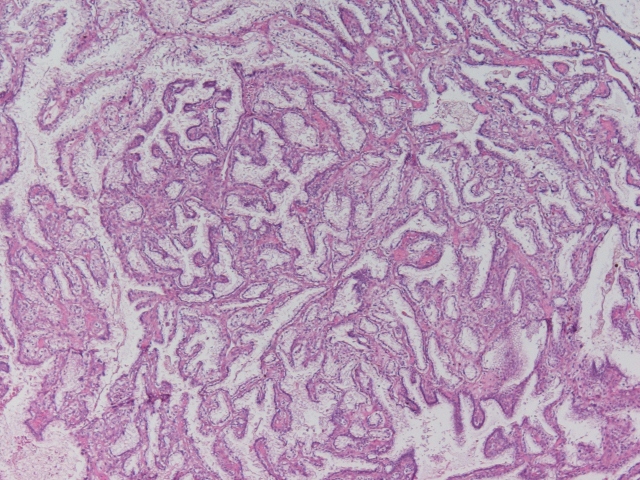

Classification of renal tumors

Case ID: 963

21 Jan, 2016